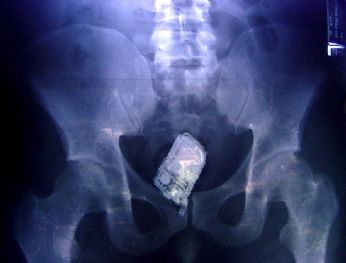

Dove nascondere la refurtiva ahuhahuahuauh

Un telefono cellulare in un’immagine a raggi x dell’intestino di un carcerato della prigione ’Mara Salvatrucha’ a San Salvador. Nei controlli a tappeto, negli intestini di quattro detenuti sono stati ritrovati 4 telefoni cellulari, nove chip e un carica batterie.